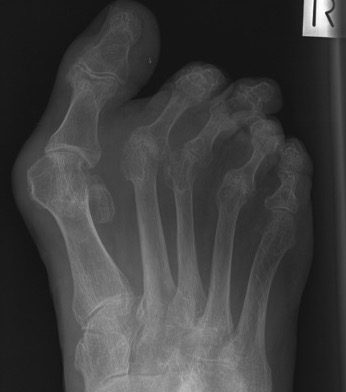

Cavus foot